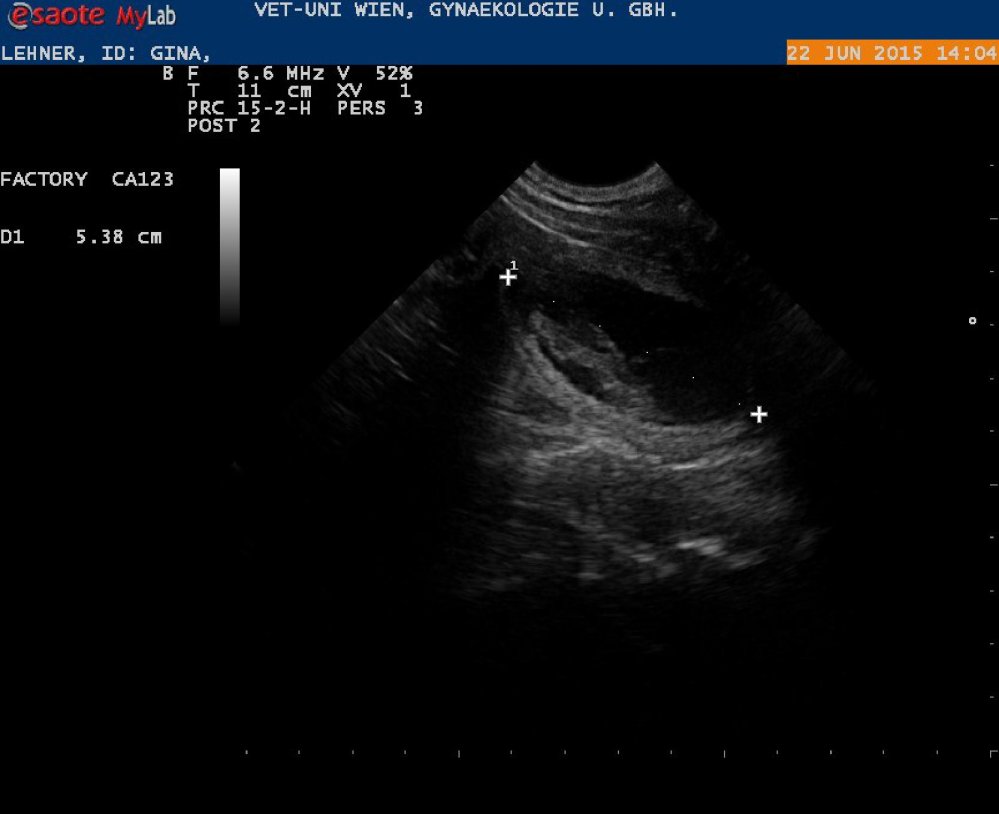

Gina wurde am 25.05.2015 von Asterix gedeckt!

Wir erwarten einen großen Wurf! (ca. 27. Juli 2015 Geburtstermin)

Ultraschall vom 28. Tag

&

Ultraschall vom 49. Tag